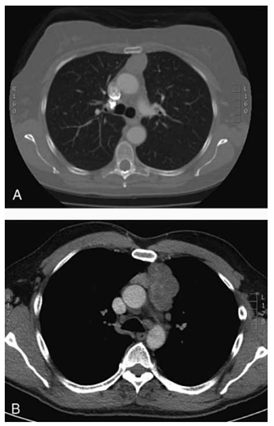

Mulher, 42 anos, queixa-se de fadiga progressiva com

diplopia ao final do dia há 6 meses. Exame neurológico

sugere fraqueza fatigável; sorologia para anticorpo anti-

-receptor de acetilcolina é positiva. Radiografia de tórax

mostra alargamento do mediastino anterior. A tomografia computadorizada de tórax com contraste mostra uma

massa encapsulada no mediastino anterior, sem invasão

evidente de estruturas adjacentes (imagem demonstrada a seguir). Não há adenomegalias mediastinais

perceptíveis.

(Townsend Jr., C. M.; Beauchamp, R.D.; B. Evers, M. and Mattox, K.L. Sabiston - Tratado de Cirurgia. 20a Edição, Ed. Elsevier, 2019, pg. 2506)

Qual a conduta mais adequada para esse caso?

(Townsend Jr., C. M.; Beauchamp, R.D.; B. Evers, M. and Mattox, K.L. Sabiston - Tratado de Cirurgia. 20a Edição, Ed. Elsevier, 2019, pg. 2506)

Qual a conduta mais adequada para esse caso?